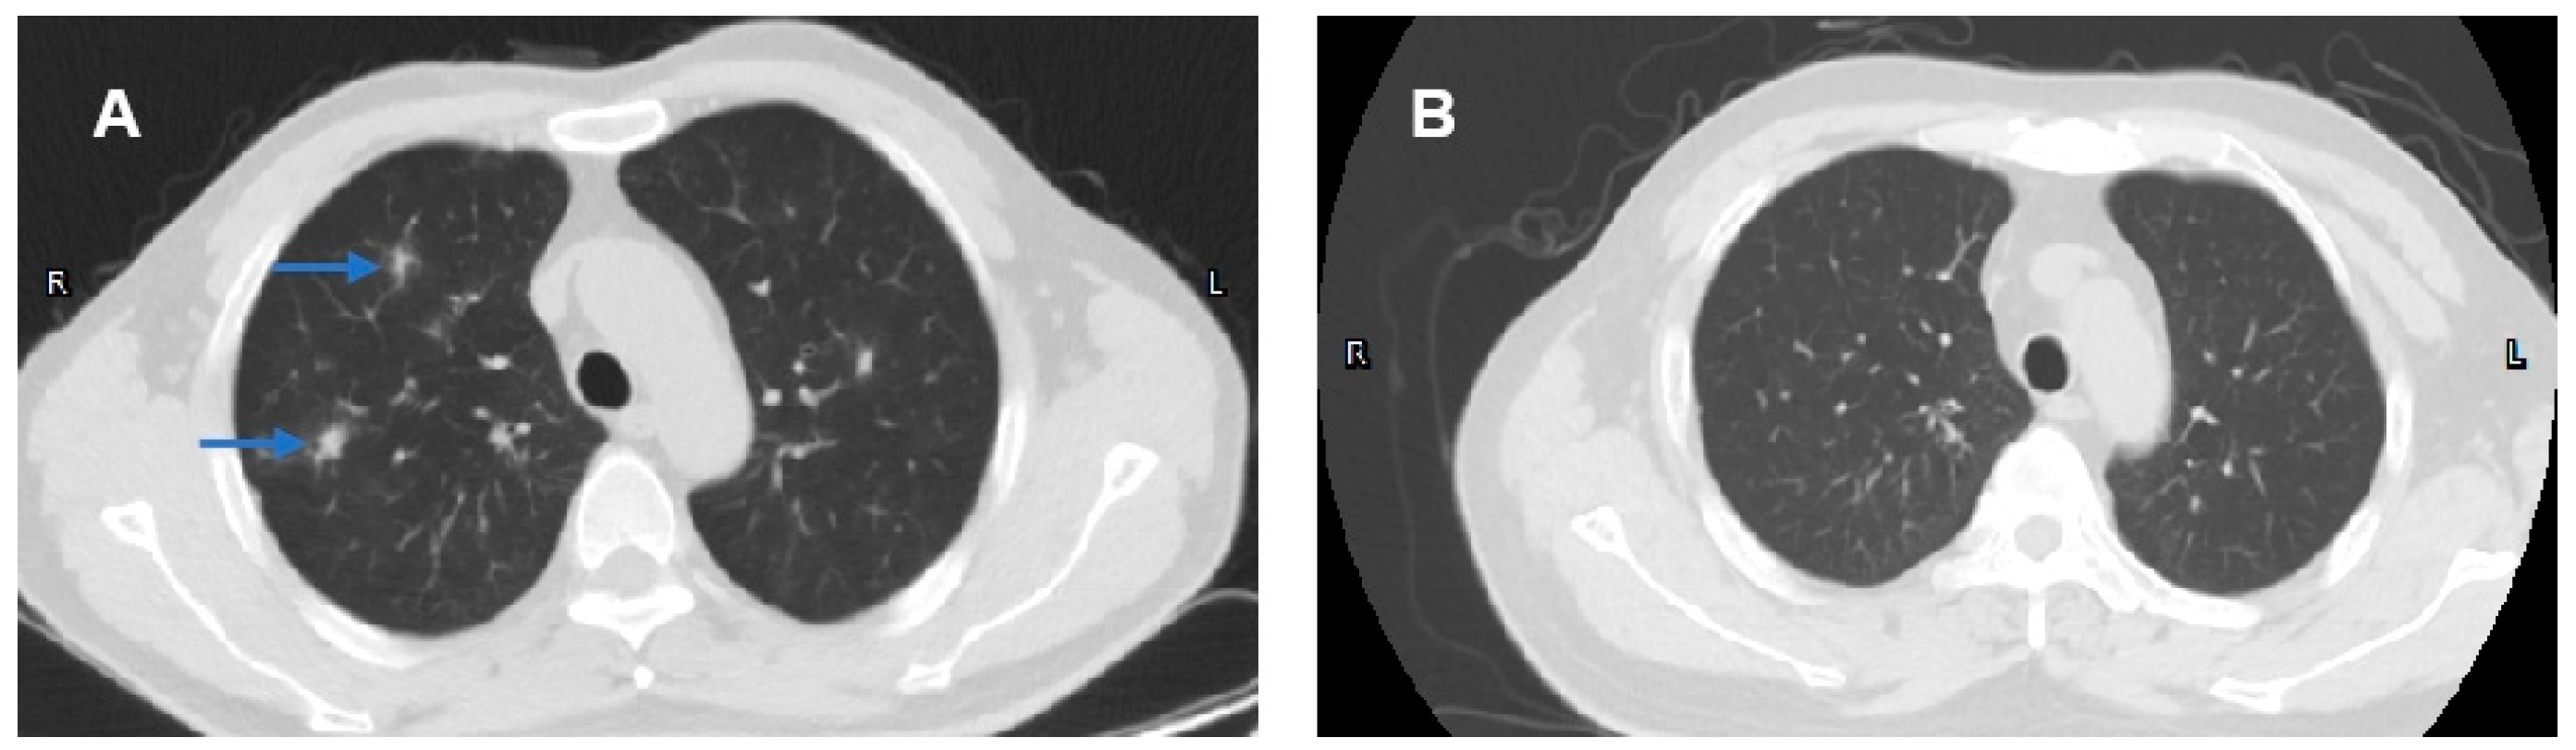

2.2. Case 2